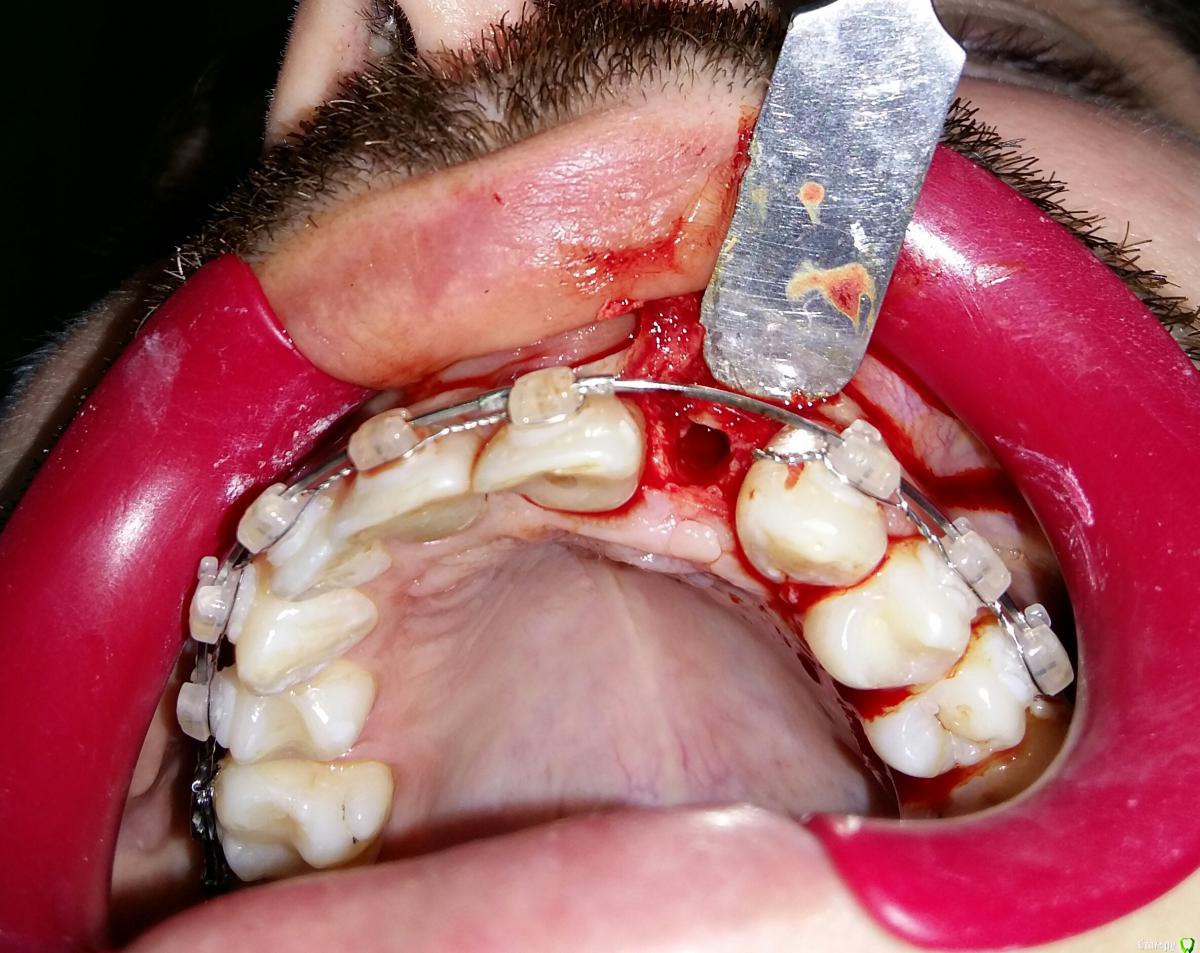

Kostoprav Опубликовано 8 июля, 2015 Поделиться Опубликовано 8 июля, 2015 ИЗНАЧАЛЬНАЯ СИТУАЦИЯ ПОЛУЧИЛОСЬ сори что нет фото до имплантации. Блок взял с тела челюсти, фиксировал двумя винтами (во время имплантации выкрутил только один), присыпал gen os, укрыл дермой-получил заметный прирост слизистой) имплант альфадент 3,75х11,5 2 Ссылка на комментарий

Kostoprav Опубликовано 8 июля, 2015 Автор Поделиться Опубликовано 8 июля, 2015 Видно что блок прирос. ЗдоровоОстальное оценить сложноМне нравится положение импланта в плане оси.Но уровень заглубления не ясенТакже не видно прироста десныВ общем мало данных для оценкиНо опять же вам именно она и нужна?по вестибюлярной поверхности заглубил приблизительно на 1мм с небной больше получилось. слизистая по сравнению с первым разом значительно толще стала, доказать к сожалению не могу так как не делал фото(: я выложил этот пост не только ради оценки, может кому из начинающих данный случай сгодиться 3 Ссылка на комментарий

Kostoprav Опубликовано 28 июля, 2015 Автор Поделиться Опубликовано 28 июля, 2015 Сколько времени прошло после фиксации блока? Чем забирает е блок? на момент имплантации 6 мес. забор блока делал линденманом Ссылка на комментарий